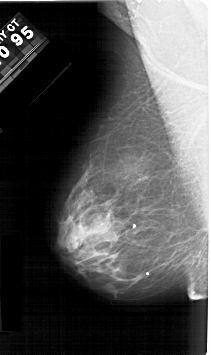

A_1533_1.RIGHT_CC

RIGHT_CC LINES 5041 PIXELS_PER_LINE 2881 BITS_PER_PIXEL 12 RESOLUTION 43.5 OVERLAY